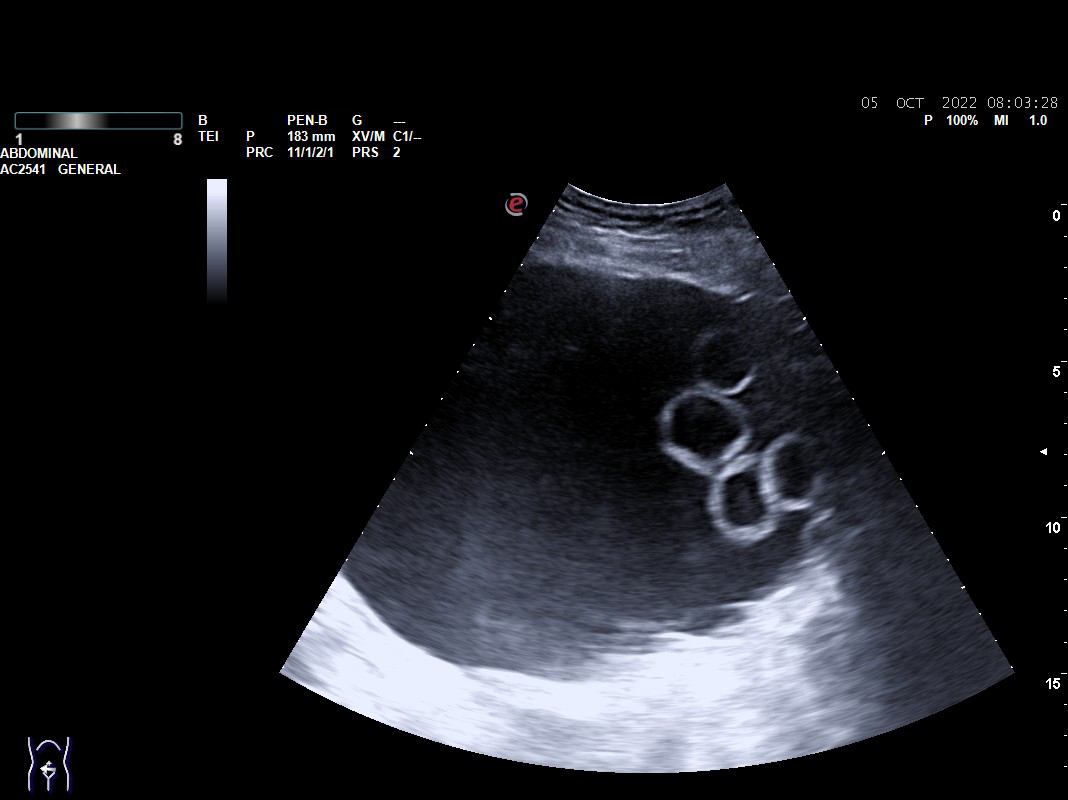

Objetivamos formación quística compleja tabicada de 17 x 10 cm con cámaras en su interior que parece depender de ovario, sin vascularización. Presencia de líquido libre en Douglas.

Con sospecha de formación anexial se deriva a Urgencias de Ginecología para valoración: exploración ginecológica normal y en Eco-Doppler-Transvaginal confirman formación multicameral sonoluscente localizada en zona central de pelvis, suprauterina hasta un través por encima de ombligo, ocupando toda la pelvis de 176 x 107 mm con múltiples cámaras en polo superior derecho. No se visualiza líquido libre en hemiabdomen superior, no impresiona de carcinomatosis  ni de dilatación de pelvis renales. Líquido libre en Douglas moderado. Sin ascitis.